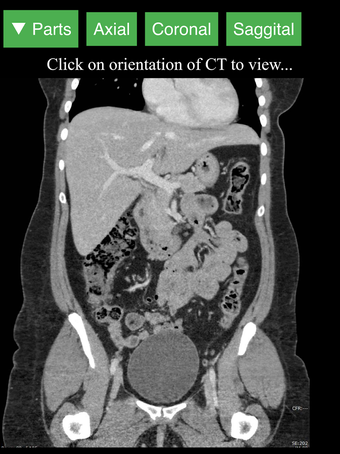

Radiology CT Viewer - полезный инструмент для врачей, медицинских студентов, радиологических техников и других медицинских специалистов, которые хотят узнать больше о человеческом теле и его анатомии. Приложение содержит подробные сечения наиболее важных частей тела. Кроме того, оно содержит интерактивную 3D-модель, которая позволяет вращать, увеличивать и перемещать камеру вокруг изображения, чтобы получить лучший обзор анатомии.

Если вы ищете инструмент, который поможет вам узнать больше о человеческом теле, Radiology CT Viewer - отличный выбор. Он содержит подробные иллюстрации и интерактивную 3D-модель.